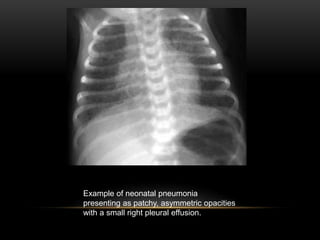

Example of neonatal pneumonia

presenting as patchy, asymmetric opacities

with a small right pleural effusion.

• Neonatal pneumonia can present with either diffuse reticulonodular

densities similar to respiratory distress syndrome or with patchy,

asymmetric infiltrates with hyperaeration similar to meconium

aspiration.

• The presence of a small pleural effusion is a useful distinguishing

feature as it is a common finding in neonatal pneumonia (up to 2/3)

and is uncommon in respiratory distress syndrome.